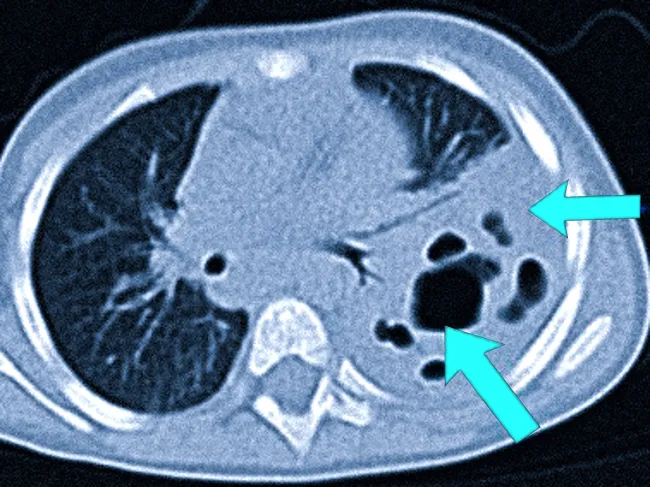

Киста легкого на КТ после COVID-19

Воспалительный процесс (обозначен красной стрелкой) и сопутствующее инфильтративное изменение (синя стрелка).

После перенесенной коронавирусной инфекции, часто осложненной пневмонией, у некоторых пациентов на фоне фиброзных изменений выявляют отдельные кисты. При диагностике важно учитывать, что «после» COVID-19 не всегда означает «вследствие» его. Врач анализирует течение заболевания, результаты клинических анализов, а также иммунный статус пациента.

Воспаление легких в комбинации с иммунодефицитом может приводить к образованию абсцессов (ограниченных гнойников в легочной ткани). При условии успешного течения заболевания и применения антибиотикотерапии гнойный детрит может рассасываться, а полости очищаться. Однако в будущем возможно развитие рубцов или воздушной кисты легкого.